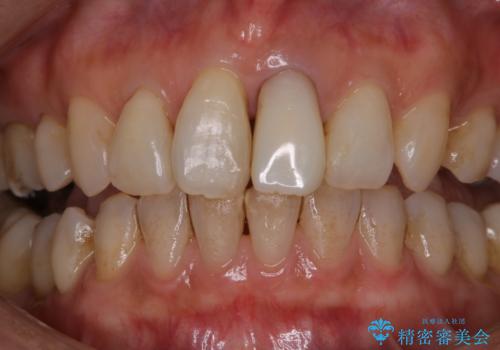

2カ月で全体的に着色(PMTC)

PMTC30分コースを行いました。